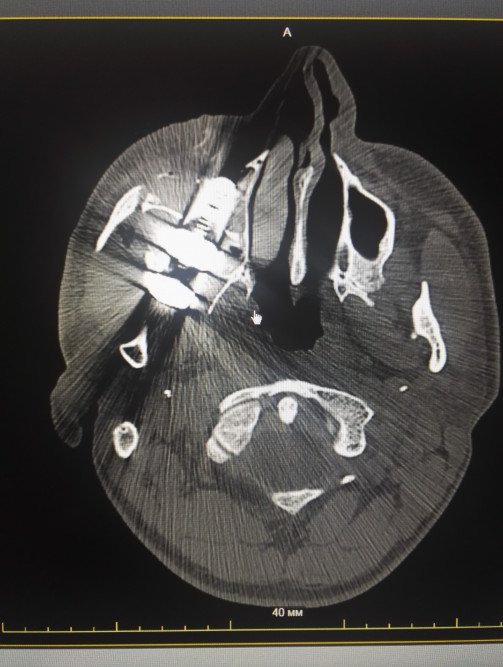

Скорая помощь доставила парня в Лесосибирскую ЦРБ, где выполнена МСКТ. К изумлению врачей под глазом Антона визуализирован крупный болт с гайкой и множественные повреждения костей лицевого черепа.

На рентгенографии придаточных пазух носа отмечается оскольчатый перелом правой скуловой кости и дуги со смещением отломков, перелом стенок правой верхнечелюстной пазухи. Инородное тело металлической плотности в области правой верхнечелюстной пазухи, размером 6,2х2,5 см.

С диагнозом - проникающее ранение лица справа инородным телом. Перелом правой скуловой кости и дуги, нижней стенки глазницы, стенок правой верхнечелюстной пазухи, инородное тело в правой крыло-небной ямке – Антон госпитализирован в отделение челюстно-лицевой хирургии.

На МСКТ после операции стояние металлоконструкций удовлетворительное.